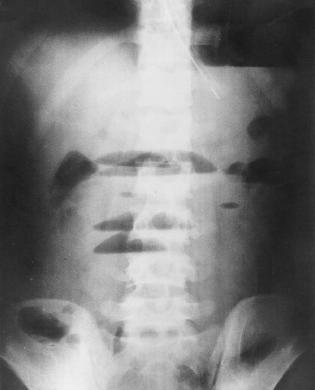

| Aspect radiologique ASP

de occlusion intestinal : Image hydro-arerique

des anses de l' intestin dilate et isolee au milieu de

l'abdomen . Les plies muqueuse de l'intestin sont

multiple et image de vide en aval de l'obstacle (

n'as pas image de air dans la region pelvienne ) |

Image en escalier typique de

occlusion de l'intestin grele . L'intestin est tres

dilate depasse 36mm de diametre et les niveaux hydrique se situe en

escalier

au milieu de l'abdomen . |

| Occlusion de l'intestin grele

avec image hydro-arerique du cadre intestinale est

en particuliairement que sa largeur est tres

etroite que la hauteur .et image de

transitionelle Region pelvienne est vite (

n'as pas de air intestinale ) . |

Image hydro -aerique en

escalier et sa largeur est tres etroite que la

hauteur . Occlusion de l'intestin grele , |